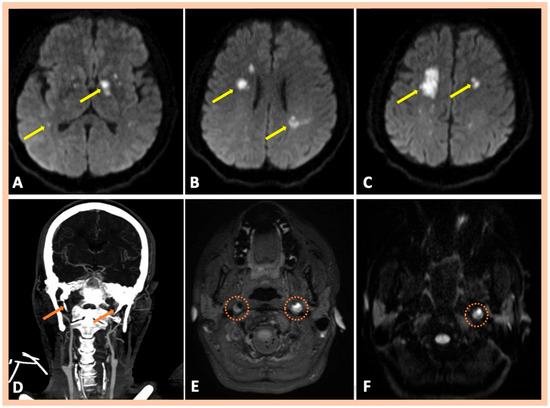

| Pat. #10 | Bilateral multiple ischemic lesions in different arterial territories | Stenosis along the distal cervical and proximal petrous segments of the right ICA. Stenosis along the distal cervical and proximal petrous segments of the right ICA. | Chronic intramural hematoma along the distal cervical segment of the right ICA. Intramural hematoma along the cervical and proximal petrous artery segments of the left ICA | Confirmed MRA findings CT revealed elongated styloid processes bilaterally, indicative of Eagle syndrome | Symptomatic right and left ICA dissections | 2 | No |